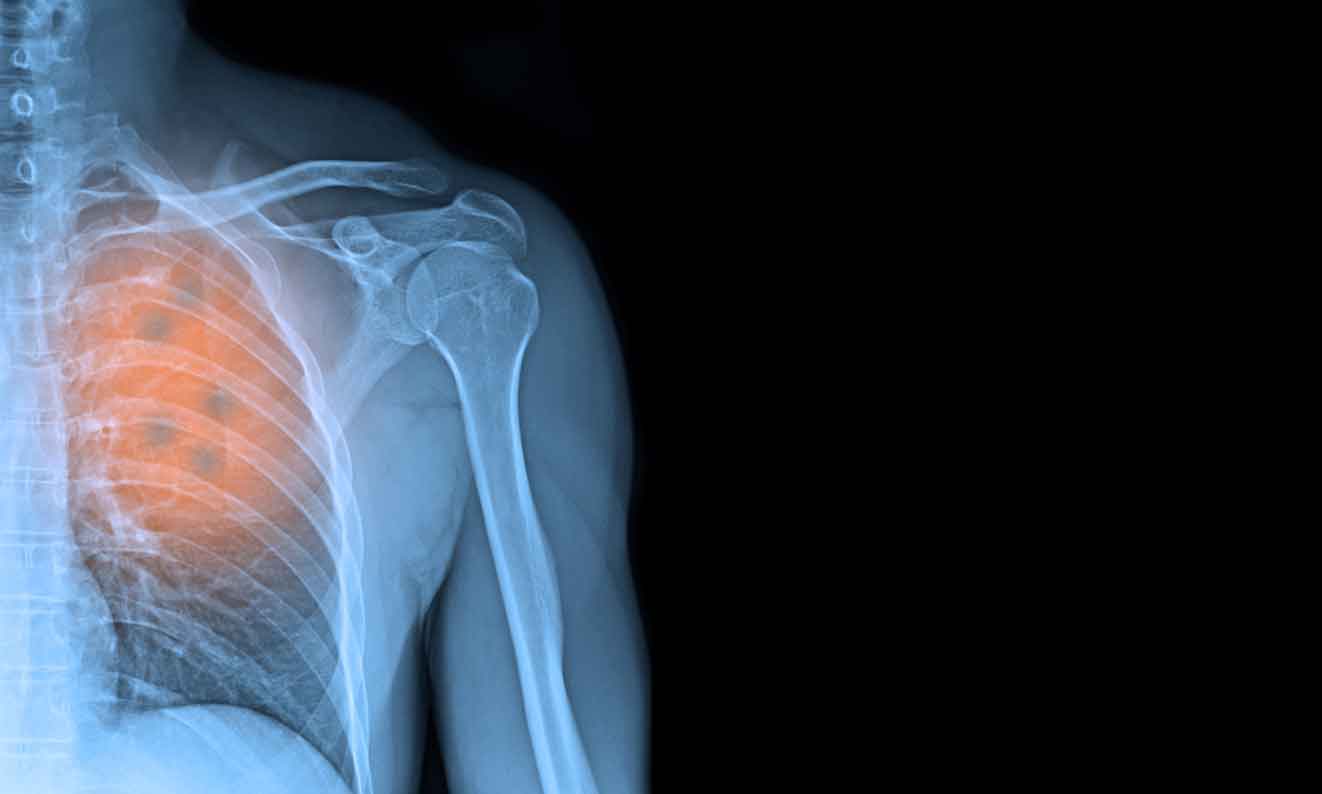

这项名为Virtual Nodule Clinic (VNC)的肺癌预测人工智能软件由Optellum(位于英国牛津)研发,将检查肺部结节以确定其是良性还是恶性。在由诺丁汉、牛津和利兹的临床医生进行的多中心研究中,这一开创性的人工智能解决方案已经被证明超越了现有的预测结节恶性的方法,结果已在去年发表在BMJ Thorax上。

肺癌是英国导致癌症死亡的首要原因,占每年所有癌症死亡的21%。在早期诊断时,英国几乎有57%的肺癌患者能够存活五年或更久,而当疾病处于晚期时,仅有3%。目前,在英国约有四分之三的肺癌病例被诊断为晚期,尽管小肿瘤在IA期治疗的生存率高达90%。